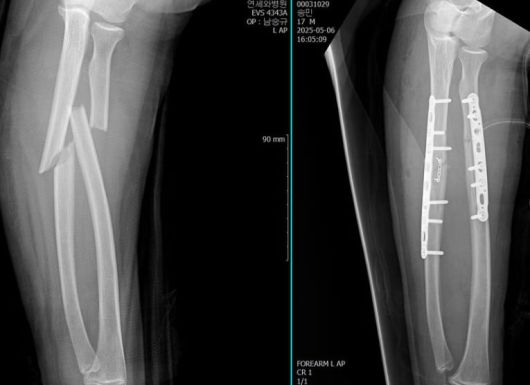

이어 "너무 막막하고 ... 어째야할지 몰라서 민이를 잘 알고 계신 원장님이 계신 병원으로 연락했어요... 인천이라 멀긴했지만 또다른 선생님께서 너무 잘 수술도 해주시고 뒤에 상처 꼬메는것과 소독까지 다 꼼꼼하게 처리해주셔서 ㅠㅠ 너무 잘 치료받고 회복하고있어요"라는 글과 함께 여러 장의 사진들을 게재했다.

공개된 사진들 속에는 오윤아의 아들의 팔이 너무나 선명하게 부러진 모습. 이에 아들은 수술을 받았고, 그 결과 깔끔해진 뼈대를 보였다. 이후 아들은 아이스크림을 먹는 등 환한 미소를 보이기도 했다.